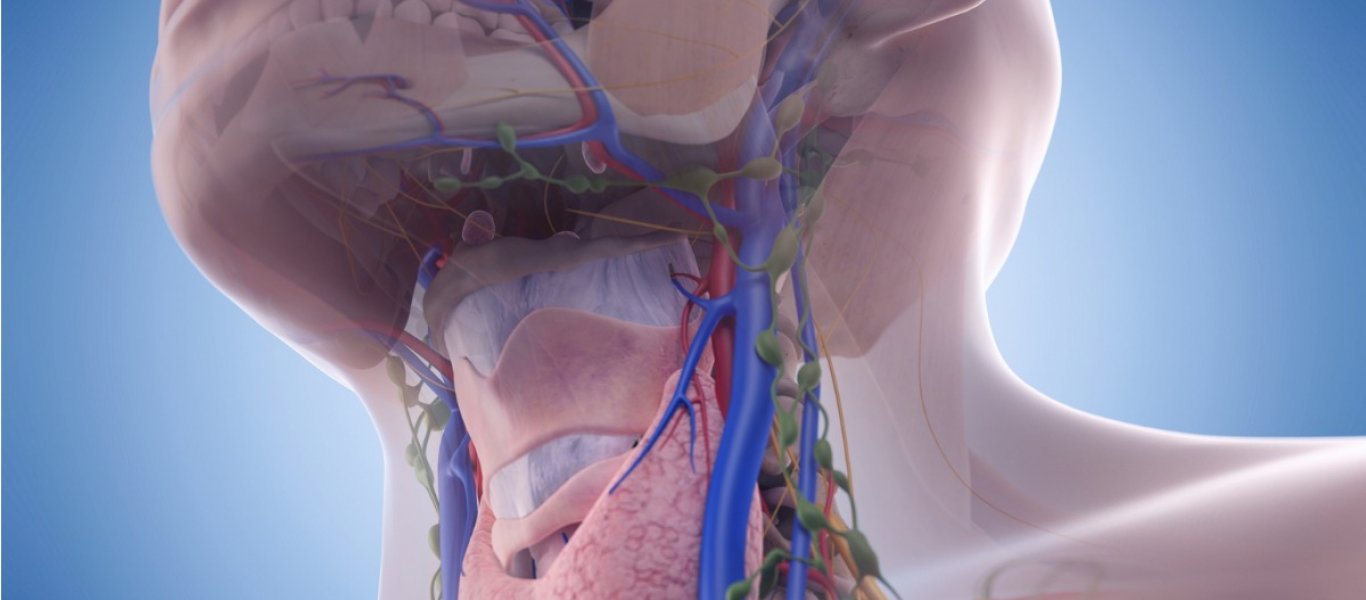

Αν είστε συνεχώς άρρωστοι ή κουρασμένοι, το λεμφικό σας σύστημα μπορεί να έχει σταματήσει να λειτουργεί σωστά.

Το λεμφικό σύστημα αποτελείται από τους λεμφαδένες, τον σπλήνα, τον θύμο αδένα και τα αγγεία που μεταφέρουν υγρά, τα οποία προστατεύουν το σώμα σας από τις ασθένειες. Αυτό το σύστημα μπορεί να γίνει υποτονικό, όταν δεν ασκείστε αρκετά, ακολουθείτε κακή διατροφή ή έχετε μια παρατεταμένη, σοβαρή ασθένεια.

Κάντε ένα λεμφικό μασάζ σε έναν εξειδικευμένο θεραπευτή μασάζ. Ο θεραπευτής θα χρησιμοποιήσει τους αντίχειρες, τα δάχτυλα και τα χέρια του για να κάνει μασάζ στους λεμφαδένες σε όλο το σώμα σας, καθώς και σε πολλά αγγεία που βρίσκονται ακριβώς κάτω από το δέρμα σας και μεταφέρουν την λέμφο, ένα άχρωμο υγρό που μεταφέρει τα κύτταρα του ανοσοποιητικού για να σας προστατεύσει από καθε ασθένεια.